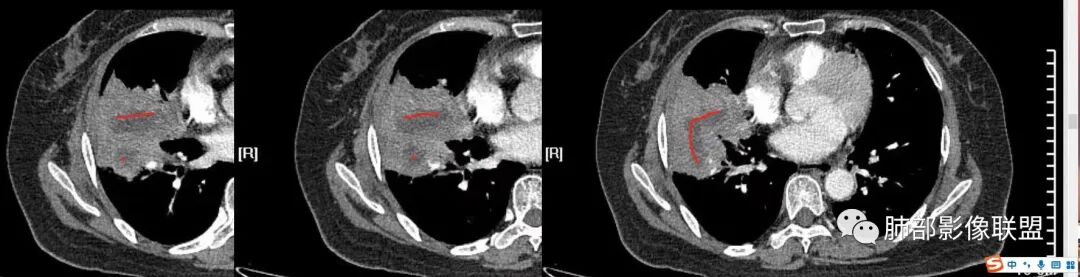

下面图片,这是腔内占位病变特点:

这是腔外为主占位特点:

这是肿瘤兼顾炎症的特点

我需要详细了解支气管、血管

南边:跨叶、楔形/边缘平直、支气管壁无破坏/连续/局部无膨大、实变区肺动脉走形自然、实性部分均匀、延迟强化、坏死腔内壁光滑/内壁强化环/近端与支气管相通,这些点均支持炎性。所以综合分析:符合炎性。